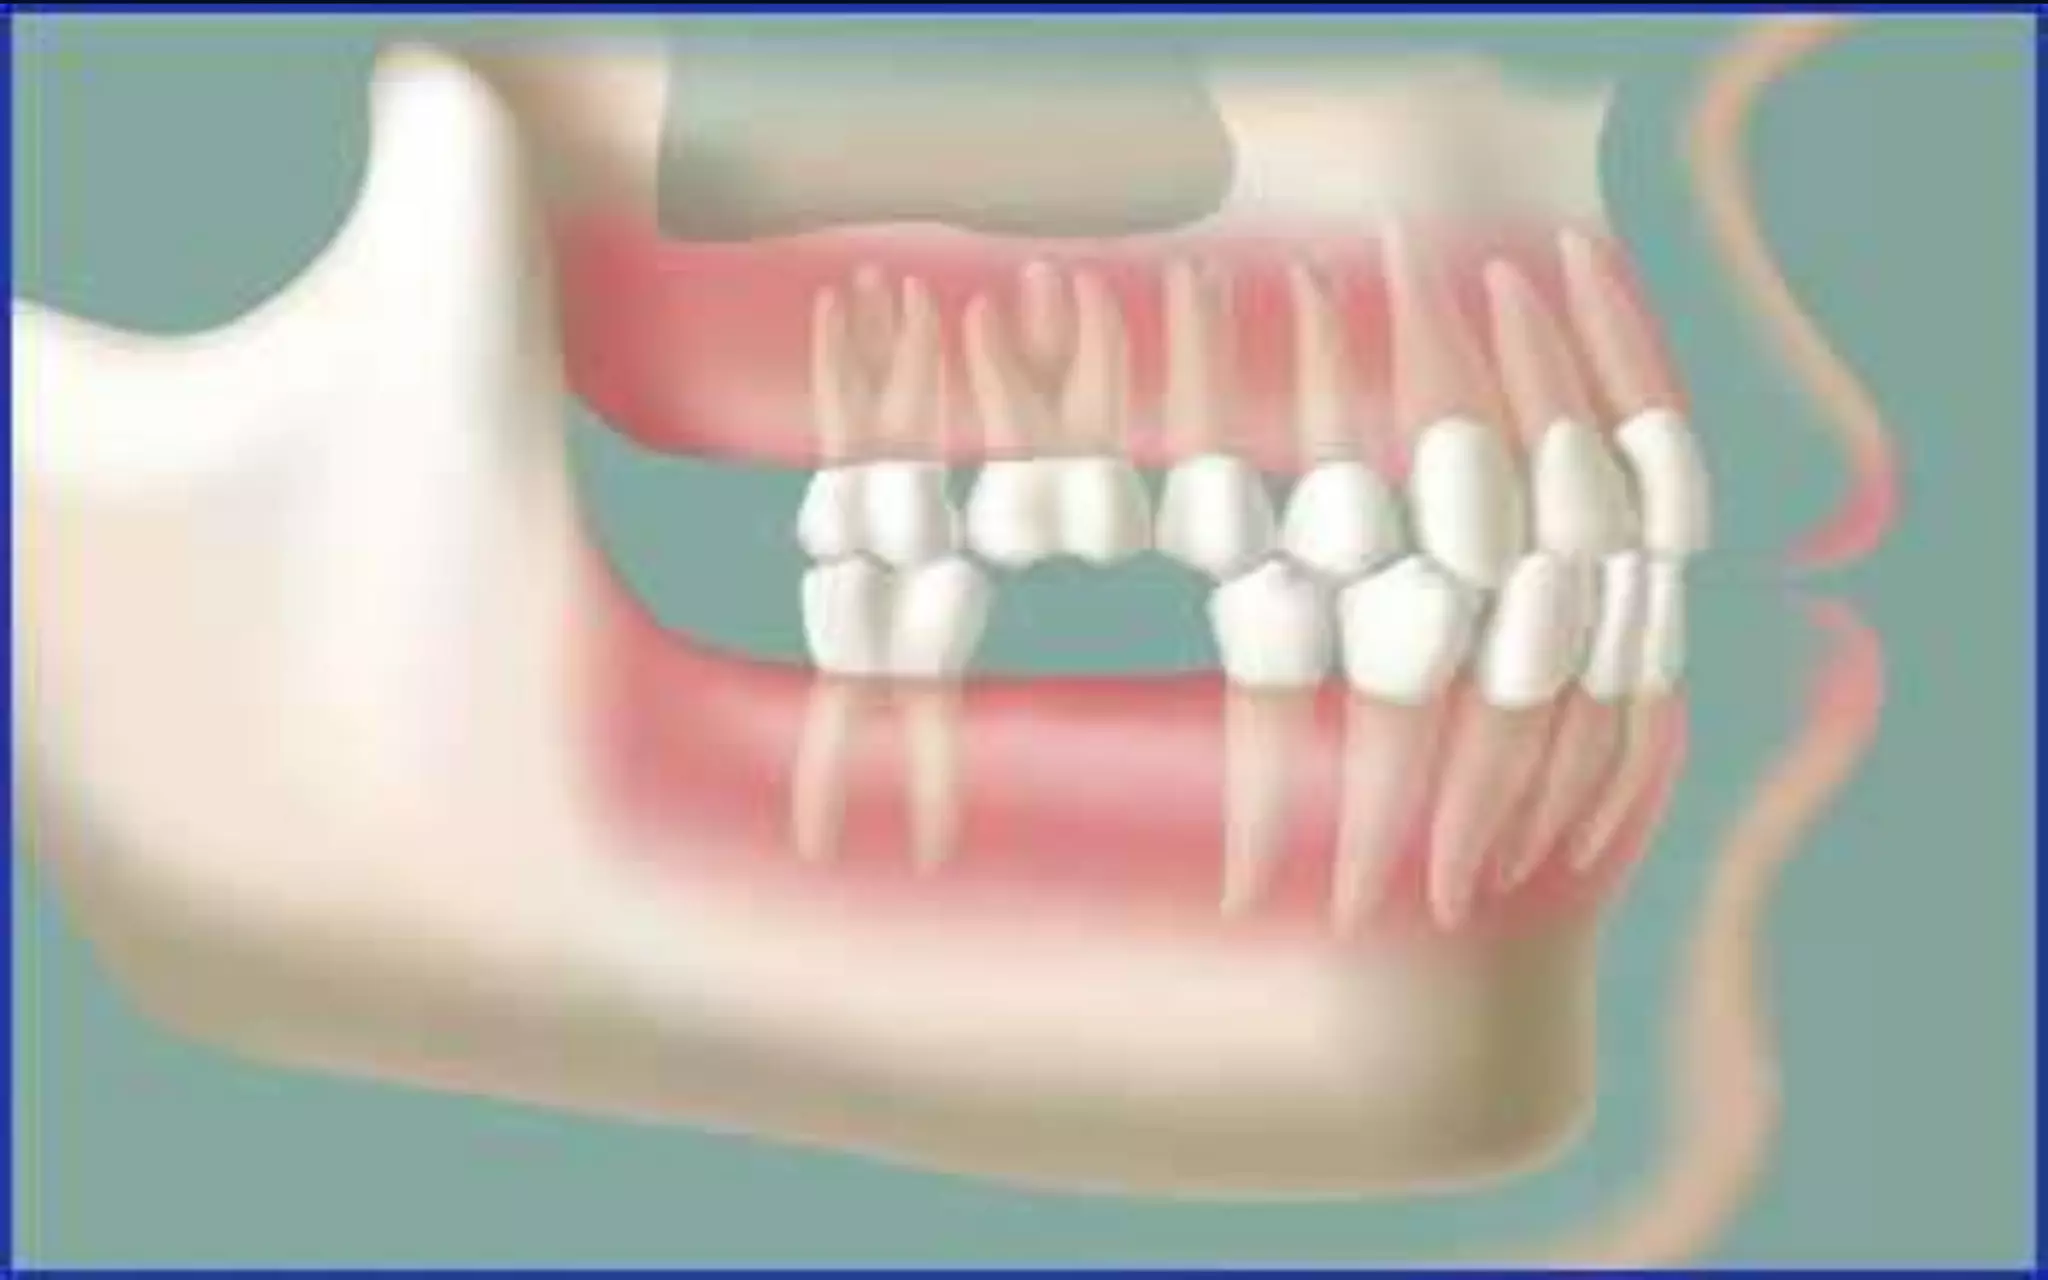

• With all the teeth present there is stability.Teeth

are not actually rigid in the mouth, but stay in

place due to a complex series of pressure

contacts and eruption

•2 lower molars missing

• Without the counter forces of the

bottom teeth , the top teeth supra

erupt

•With all teeth present there is stability.

Teeth are not actually rigid in the

mouth ,but stay in place due to

complex series of pressure contacts

and erruption forces